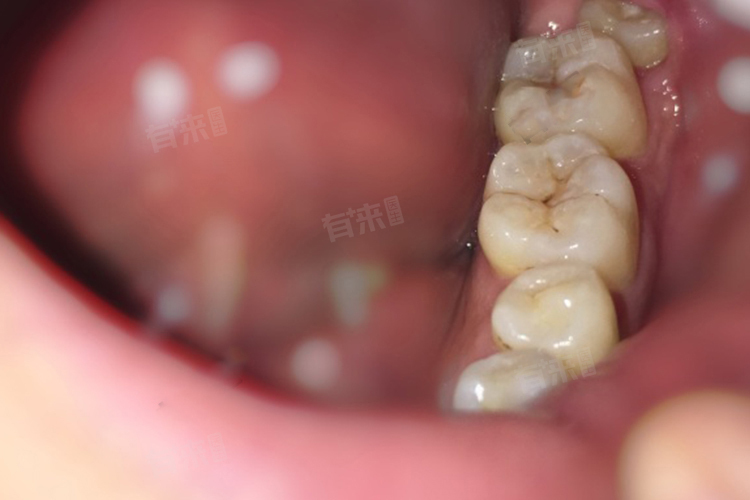

- 如果智齿发生龋坏,且龋坏程度较严重,无法通过补牙等方法进行修复,也可以考虑拔掉智齿。因为智齿位于口腔的最后部,刷牙时不易清洁到,容易滋生细菌,导致龋坏进一步发展。龋坏的智齿可能会引起疼痛、肿胀等不适症状,影响患者的生活质量。

- 如果智齿能够正常萌出到口腔内,并且与对颌牙有良好的咬合关系,不影响咀嚼功能,也没有引发其他口腔问题,可以考虑保留智齿。保留正常的智齿可以发挥一定的咀嚼功能,也可以避免拔牙带来的创伤和风险。